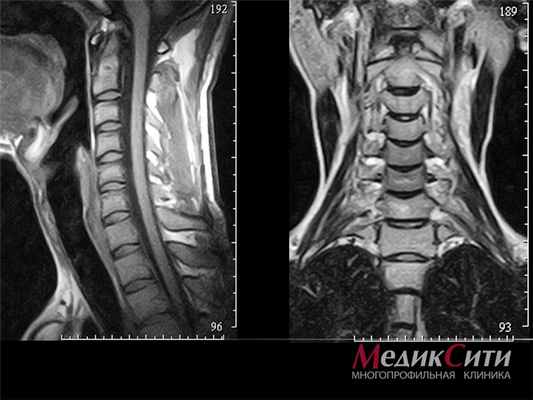

МРТ шейного отдела позвоночника: норма

Шея вмещает в себя много органов. На МРТ шеи видны позвоночник, горло, гортань, трахея, щитовидная и паращитовидная железа, кровеносные сосуды и др. Шея – это анатомическое наиболее подвижна часть тела. Поэтому наиболее частым объектом исследования при МРТ шеи является шейный отдел позвоночника. МРТ исследование показывает состояние не только шейных позвонков, но и дисков. Как правило проводится измерение сечения позвоночного канала на уровне выпячивания дисков, что есть крайне важной информацией для принятия решения о лечении. Следует отметить, что эти показатели важны при МРТ исследовании любого отдела позвоночника.

На МРТ шеи виден спинной мозг. Современные аппараты позволяют уточнить состояние тканей спинного мозга, вовремя выявить т.н. миелопатию (изменение структуры спинного мозга).

Важной особенностью шеи есть то, что через нее проходят сосуды, которые питают головной мозг. Это сонные и позвоночные артерии. Сосуды шеи – один из объектов исследования при МРТ шеи. Исследование сосудов шеи, как правило проводится вместе с сосудами головы (МРТ головы и шеи). По своей сути эти сосуды являются одним целым и предусматривает диагностику сосудов головы и шеи одним пакетом.